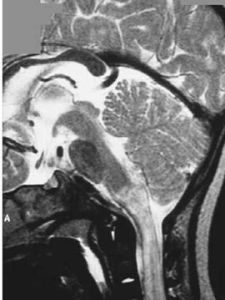

腦幹腦炎患者,女,35歲,湖南衡陽市郊農民。因行走無力,視物模糊5天,加重伴言語不清,嗜睡2天,於2005年11月24日急診入院。2005年11月20日上午,患者在廣州某鎮探親時家務勞動後,上樓時出現行走無力,下午自覺視物模糊,不伴發熱、惡寒、頭痛、頭暈、咳嗽、咽痛、噁心、嘔吐等症狀。11月21日上午患者步行到廣州市某鎮醫院按"上呼吸道感染"治療無效。11月22日下午患者出現行走無力加重,需人攙扶,並出現言語欠清晰、精神差,被家人於當晚送回湖南當地縣人民醫院診治。查體:嗜睡,反應遲鈍,言語欠清晰,口角向左歪,伸舌右偏,右上下肢肌力IV級,左上下肢肌力正常,病理反射(-)。頭顱CT平掃未見異常。按"腦梗塞"治療病情無好轉,故於11月24日下午轉至我院神經內科重症監護病房按重症腦梗塞診治。入院時查體:T36.7℃P86次/分R20次/分BP105/71mmHg嗜睡,言語欠清晰,右眼瞼稍下垂,右眼內收及左眼外展受限,右側鼻唇溝稍變淺,伸舌右偏,雙側咽反射減弱,心、肺、腹均未見異常,左上、下肢肌力IV級加,右上、下肢肌力III級加,四肢肌張力稍低,腱反射減退,指鼻及輪替試驗及感覺功能檢查無法配合。頸軟,克、布氏征(-),右巴氏征(+),左巴氏征(-)。實驗室檢查:血常規:WBC總數:10.4×109/L,分類正常;電解質、肝、腎功能、血脂、血糖及血氣分析均正常。11月25日上午患者出現昏睡,完全性失語,四肢肌力明顯減退,右上肢肌力0級,左上、下肢及右下肢肌力均II級。查頭顱MRI示:中腦與橋腦交界處見片狀稍長T1稍長T2信號,邊界欠清晰,中腦導水管及第四腦室未見明顯受壓;頭顱MRI增強:腦幹異常信號,未見明顯強化,考慮腦幹梗塞。11月26日患者陷入淺昏迷,腰穿查腦脊液壓力95mmH2O,外觀無色,清亮,潘氏實驗(+),總蛋白定量0.58g/L,白細胞數76×106/L,單個核細胞90%,多個核細胞10%,葡萄糖2.59mmol/L,氯化物117mmol/L,故診斷為腦幹腦炎,給予地塞米松10mg靜滴,每日一次,同時予抗病毒,抗感染等治療,12月2日患者意識轉清醒,但言語模糊不清,右上肢肌力II級,右下肢肌力0級,左上下肢肌力II-III級。14天后停地塞米松改為口服強的松30mg/天,逐漸減量,患者入院第20天因經濟困難出院,出院時查體:右眼內收及左眼外展受限,伸舌稍右偏,雙上肢肌力III-IV,雙下肢肌力III級,病理征陰性,複查腦脊液:壓力180mmH2O,無色,清亮,潘氏實驗(-),腦脊液蛋白定量0.23g/L,白細胞數16個106/L,單核細胞為主,葡萄糖3.4mmol/L,氯化物128mmol/L。2006年1月17日複診:患者仍行走不穩,需人攙扶。查:神清語利,計憶力、定向力、記算力正常,雙眼球運動正常,雙鼻唇溝對稱,伸舌稍右偏,四肢肌力肌張力正常,雙巴氏征陽性,深淺感覺檢查正常。雙側指鼻試驗稍差,Romberg征睜眼(+),閉眼(+)。腦電圖正常;視覺、腦幹聽覺誘發電位檢查:右眼VEP潛伏期延長,波幅在正常範圍內;左眼VEP潛伏期、波幅在正常範圍內;右耳BAEP波形分化不良,左耳BAEPⅠ、Ⅲ、Ⅴ波幅,潛伏期正常;四肢肌電圖檢查:左腓總神經運動傳導波幅降低。2006年3月15日隨訪,患者行走正常,完全康復。查體無異常。